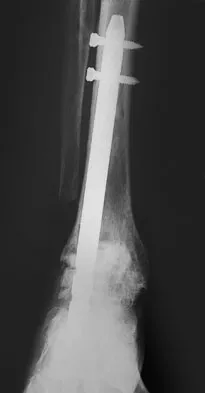

A patient with rheumatoid arthritis with both ankle and subtalar involvement was treated as shown in Figures 11a and 11b. What complication is unique to this type of fixation?

Explanation

The interlocking screws at the proximal end of the rod can act as a stress riser and lead to fracture. Postoperative pain at this level should prompt inclusion of this diagnosis in the differential. Removing the screws following bone union can decrease the chances of this occurring. A short rod that avoids the diaphyseal area may also be beneficial. Rotatory deformity is controlled by the perpendicularly oriented distal transfixion screws. Talar osteonecrosis would be unusual since the dissection can be minimized with an intramedullary rod. Any type of hardware can fail if the construct does not lead to a solid arthrodesis. Nunley JA, Pfeffer GB, Sanders RW, et al (eds): Advanced Reconstruction: Foot and Ankle. Rosemont, IL, American Academy of Orthopaedic Surgeons, 2004, pp 236-237. Thordarson DB, Chang D: Stress fractures and tibial cortical hypertrophy after tibiotalocalcaneal arthrodesis with an intramedullary nail. Foot Ankle Int 1999;20:497-500.